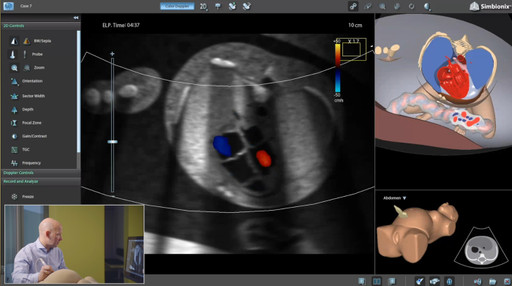

In the pursuit of excellence in fetal echo training, Dr. Steinhard's presentation introduced an existing approach used by multiple medical specialties, but with a potential to be more widely used within fetal echo training: simulator-based learning. The Ultrasound Mentor simulator by Surgical Science was highlighted as a powerful tool for training medical professionals in mastering fetal echo techniques.

This validated approach involved a phased training process, starting with an introduction to the simulator and hands-on practice. The pivotal aspect of the training was the encouragement of independent practice, allowing students and physicians to refine their skills with minimal assistance. The results, as presented by Dr. Steinhard, were significant. Participants in the training program exhibited improvements in their scanning skills, eventually reaching a proficiency level equivalent to that of experts in the field.